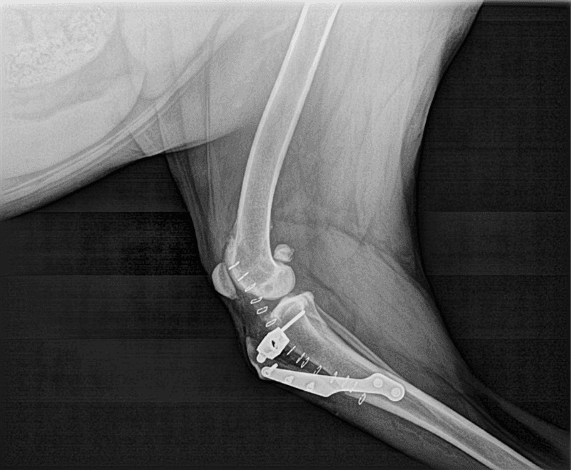

Ortopedia è una specialità veterinaria incentrata sulla diagnosi e la riparazione delle lesioni che coinvolgono ossa, articolazioni e legament.

Grazie alla presenza,preparazione e continuo aggiornamento del nostro chirurgo ortopedico, grazie alla messa a disposizione di più moderno strumentario e condizioni igienico – sanitarie della struttura, la nostra clinica è in grado di offrirVi, in ogni momento, prestazioni ortopedico – traumatologiche di alto livello.

Particolare attenzione si dedica ad un attento studio radiografico preventivo, effettuato alle razze dei cani che hanno un'alta percentuale di malattia ortopedica ereditata(displasia dell'anca e del gomito,lussazione della rottula) in un periodo compreso tra 4-5 mesi d’età.

Sono diverse le patologie ortopediche che interessano la articolazione del gomito, articolazione della spalla e articolazione dell’anca del cane. Problemi di lussazione della rotula in cani di piccola taglia e non, procedure di carattere chirurgico – traumatologico dell’ossa e dei tessuti moli periarticolari.

Abbiamo le competenze e le attrezzature moderne per diagnosticare con precisione e trattare una vasta gamma di problemi ortopedici.

Lo Staff chirurgo specializzato in chirurgia ortopedica e traumatologia, studi radiografici, test di laboratori pre operatorio, monitoraggio e terapia prima,durante e dopo la chirurgia, trattamento del dolore perioperatorio fano parte di un complessa attività diagnostico-chirurgica, che con esito finale porta a benessere animale da punto di vista ortopedico.

Placche ossee sono uno dei più forti e più efficaci metodi di fissazione di una frattura. Esse contrastano le forze di compressione, torsione e forze di trazione. Una placca ossea un pezzo in acciaio con fori per viti che stabilizzano la placca all'osso.